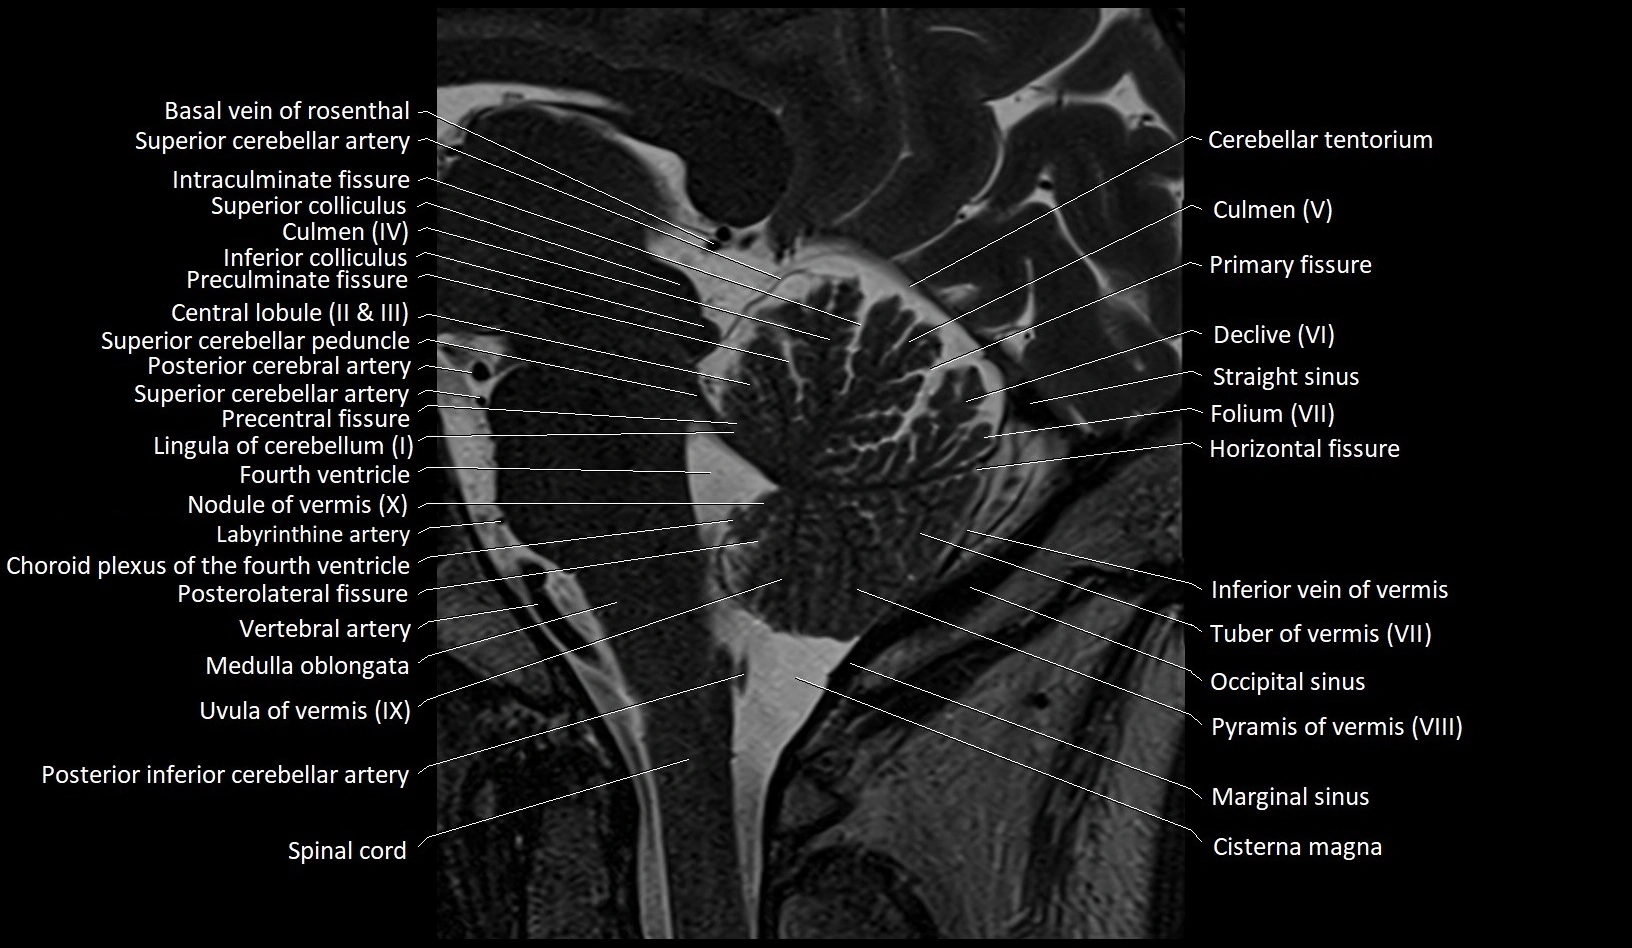

MRI images